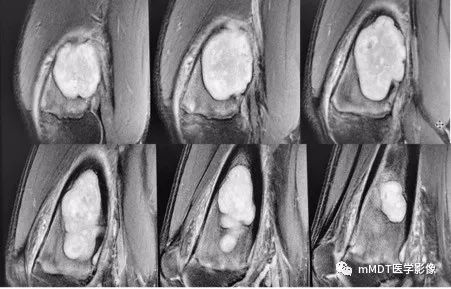

MRI矢状面T1WI序列

MRI矢状面脂肪抑制序列

CT见病变位于股骨远端干骺端,呈分叶状、偏心膨胀性生长,密度欠均匀,整体低于肌肉密度,部分区域密度接近水,其内可见点状、线状、弧形、圆形的高密度影,大部分边缘硬化,局部深侵蚀骨内膜,局部骨壳不完整。MR上,T1WI信号略低于肌肉,T2压脂呈现不均匀高信号,未见明确软骨小叶结构及纤维分隔,周围可见水肿。